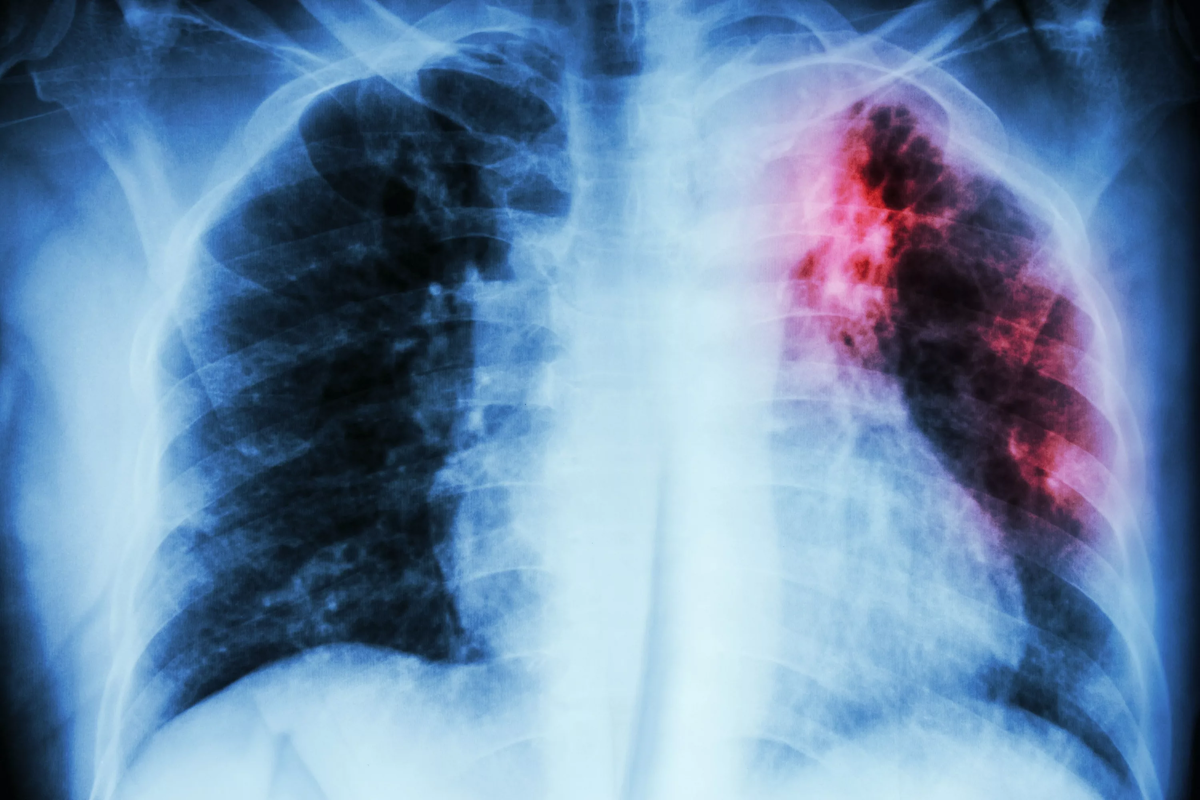

Туберкулез (от лат. бугорок)

Основной возбудитель – микобактерия туберкулеза (Mycobacterium tuberculosis). Раньше бацилла Коха. Заражает все кроме ногтей и волос.

Проявление туберкулеза:

· кровохарканье

· потоотделение

· повышение температуры в вечернее время

· снижение массы

· потеря аппетита

· длительный кашель (от 3-х недель)

Формы

· открытая форма, когда при посеве выделяется возбудитель

· закрытая – не выделяется, то есть возбудитель не выходит в мокроту

Диагностика: